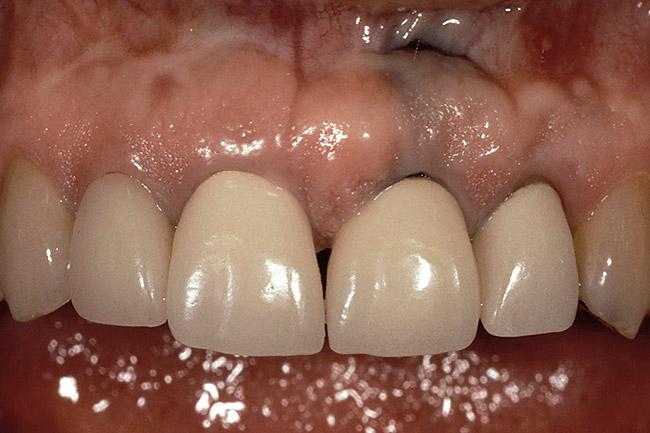

Figure 3  Dark teeth or teeth requiring restorations that are more opaque for masking often require the margin to be carried subgingivally, as with this central and lateral incisor.

Figure 3

Figure 4  View of the completed central and lateral incisor with margins placed subgingivally, but maintaining tissue health.

Figure 4

The most common reasons to extend a margin below tissue are: caries below gingiva; old restorations that already exist below gingiva; to achieve adequate tooth preparation length for proper retention and resistance; to make significant contour alterations; to hide the margin when the tooth is discolored (Figure 3 and Figure 4); and to hide the margin when the restorative material of choice demonstrates optical properties different from those of the natural tooth such that the margin would be highly visible. Regardless of why a subgingival margin is chosen, there are 2 negative responses that may occur.